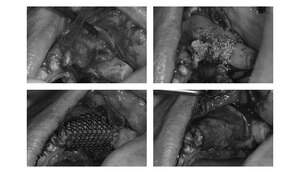

歯周病や歯の根の病気など何らかの理由で抜歯を余儀なくされインプラント治療を行う場合、抜歯後の処置予定部の骨が大きく失われていることがほとんどです。

インプラント治療を行うためにはインプラントを支える骨がないと正しく治療ができません。そのため、理想的な治療を行うために骨造成を必要とする場合があります。

主に骨の高さや幅が足りない際に行う骨造成です。骨造成量に応じて使用する材料が変わります。

主に上顎に対して行います。上顎洞の中に骨を足しインプラントの足場を作ります。

骨が大幅に無いケースや範囲が大きいときはこちらを選択します。

骨造成の範囲が少ない場合にこちらを用います。

| GBR | 110,000円 |

| GBRオプション(チタンメッシュ使用) | 88,000円 |

| サイナスリフト | 330,000円(片顎) |

| ソケットリフト | 165,000円(1本) |